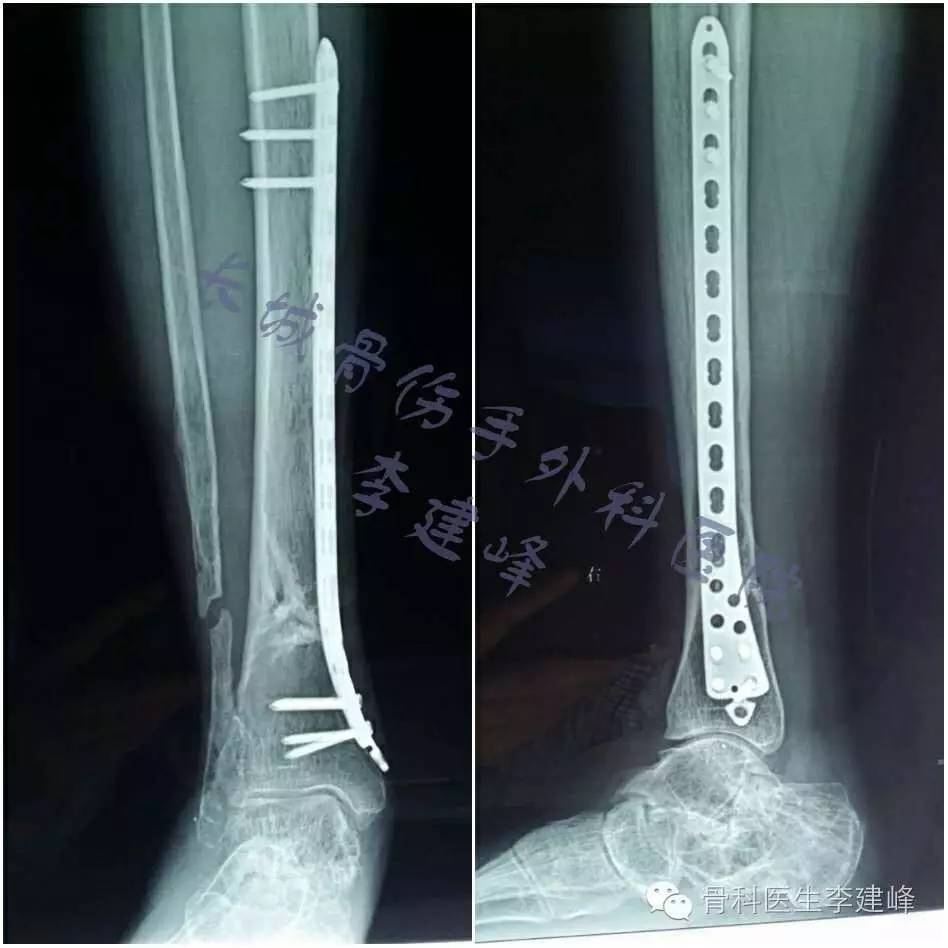

腓骨钢板图片 第1页 一起扣扣网

腓骨骨折手术图片 第1页 图说健康

我们的微创之路 胫腓骨骨折微创经皮钢板内固定 Mpo 术 骨二科

微创手术治疗胫腓骨骨折